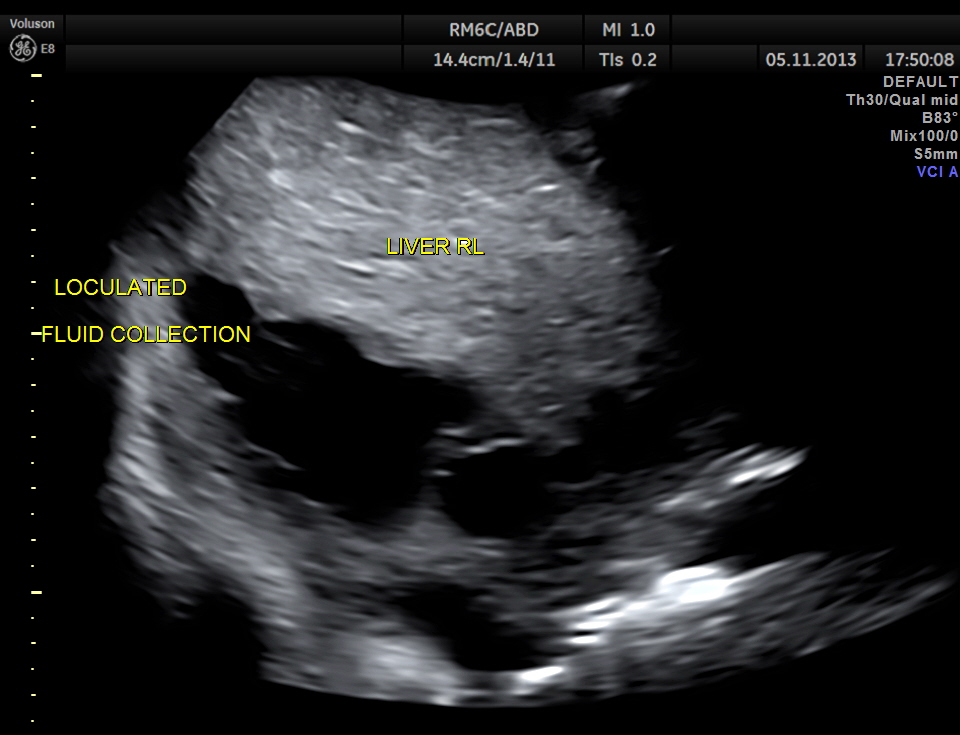

Loculated sub diaphragmatic fluid collection.

This patient had a painful metastatic nodule in the right lobe of the liver. He also had loculated sub diaphragmatic collection and a septated cystic mass in the free surface of the liver.